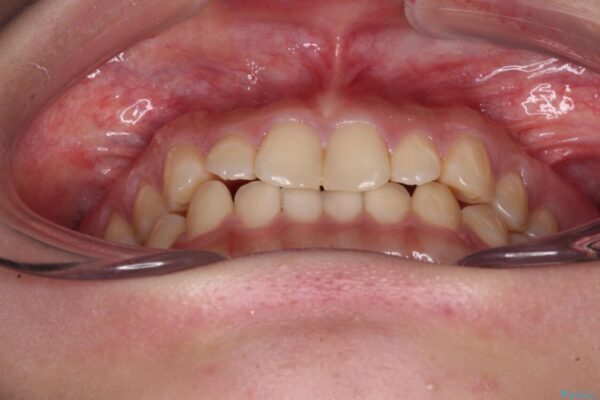

根管治療を行ったままの奥歯と、矯正治療の後戻りを気にして来院された患者様です。

矯正治療の後戻りは軽微であったため、インビザラインの簡易パッケージであるインビザライン・ライトを用いて歯列を整えることとしました。

治療途中

• 治療途中の奥歯と矯正治療の後戻り インビザライン・ライトによる矯正治療 治療途中画像